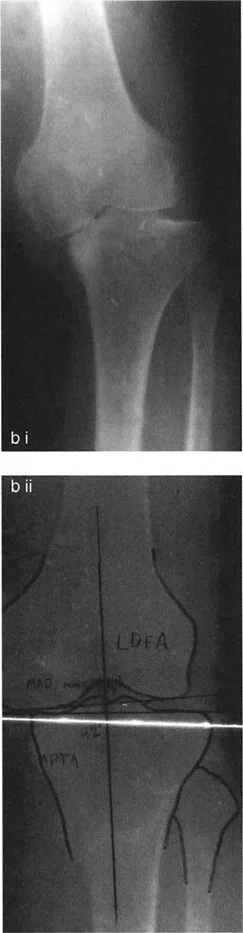

- الأشعة السينية الطويلة للطرف السفلي بالكامل أثناء الوقوف (Standing Long-Leg AP View): تُعد هذه الأشعة حاسمة لتقييم المحاذاة الميكانيكية للطرف السفلي بأكمله. تُظهر بدقة درجة الانحراف الأفحج (Varus) أو الأروح (Valgus) وتساعد في تحديد مركز دوران التشوه (CORA).

- الأشعة الجانبية الطويلة للطرف السفلي بالكامل أثناء الوقوف في أقصى بسط (Standing Long-Leg Lateral View in Maximum Extension): تُستخدم لتقييم تحدد حركة الركبة (FFD) والركبة الارتدادية (Recurvatum)، وتحديد ما إذا كان التشوه عظميًا أو ناتجًا عن تقلص في الأنسجة الرخوة.

من خلال الجمع بين الفحص السريري الدقيق والتحليلات التفصيلية للصور الشعاعية، يتمكن الأستاذ الدكتور محمد هطيف من تحديد الأسباب الكامنة وراء آلام الركبة وتشوهاتها، وتصميم خطة علاجية فردية تهدف إلى استعادة وظيفة الركبة وتخفيف الألم.